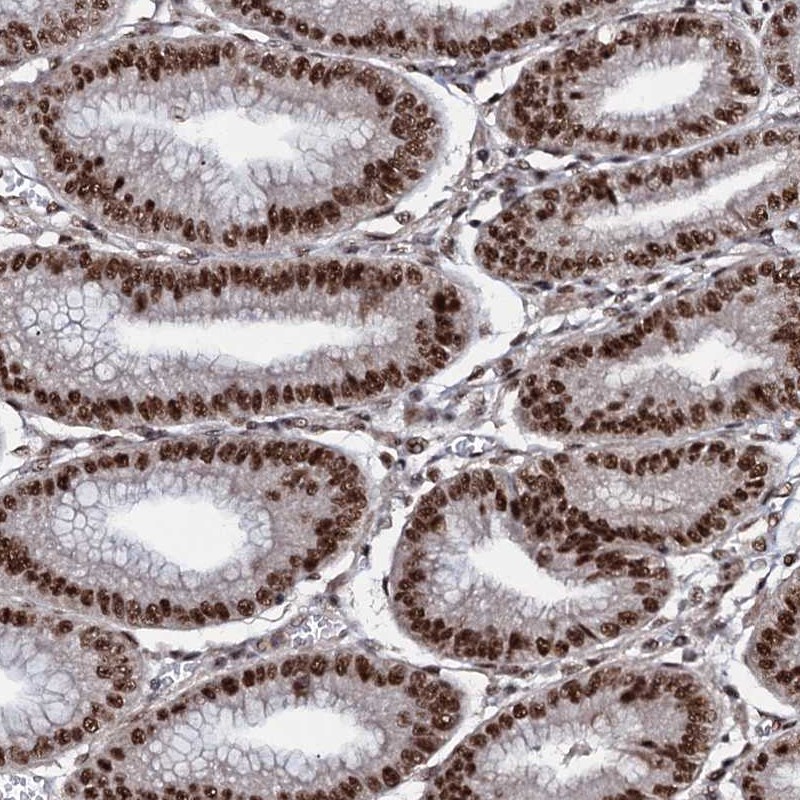

Immunohistochemical staining of human stomach shows strong nuclear positivity in glandular cells.